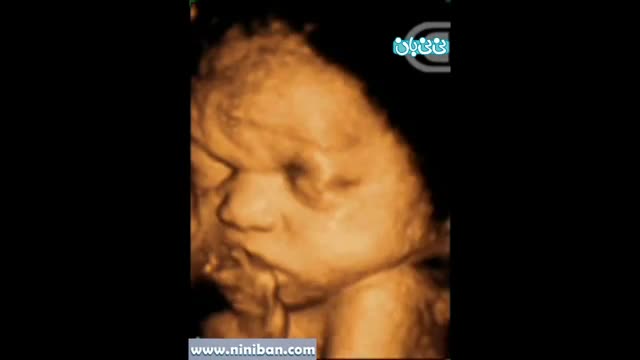

سونوگرافی چهار بعدی در بارداری هفته سی و سوم

۴ سال پیش

160015 بازدید